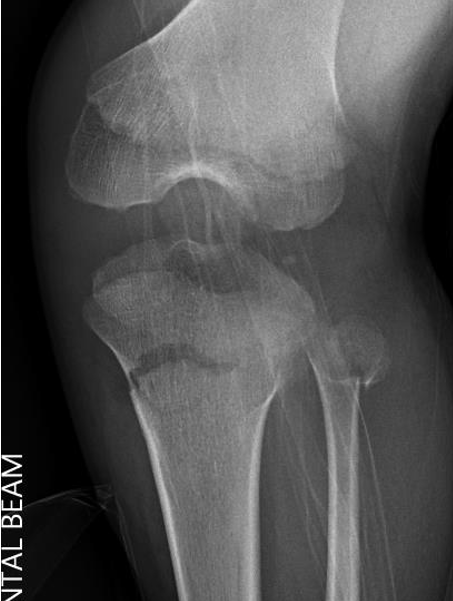

Manipulation and casting of malaligned Cozen fracture under anesthesia

Valgus malalignment